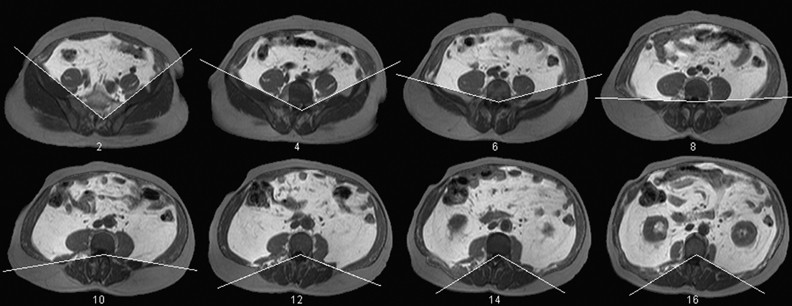

Figure 10

Illustration of the pelvis model: every second slice is shown. The white lines represent the mean pelvis model. The region affected anterior to the pelvis model, and inside the SAT, is given slightly brighter pixel values. SAT, subcutaneous adipose tissue.